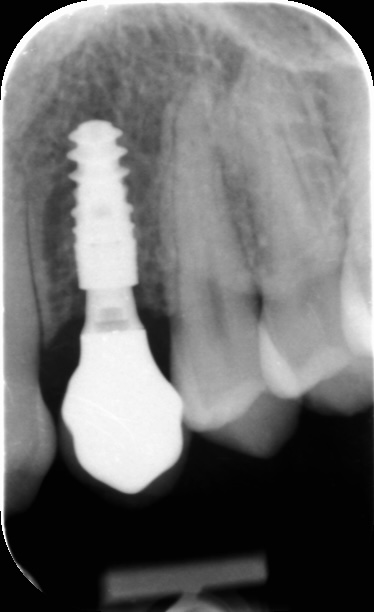

PA X-Ray with stabile marginal bone